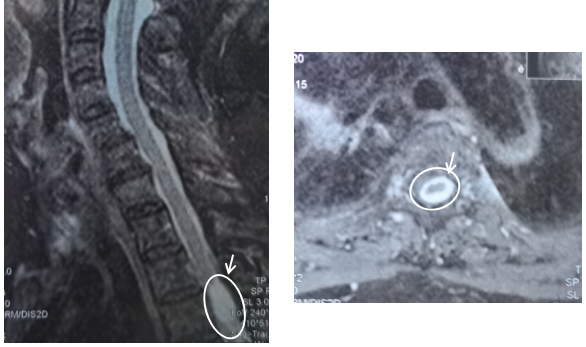

冯奶奶MRI,箭头所示为椎管内肿瘤。

说起来,咱今天为啥要说椎管内肿瘤呢?那还得从一位冯奶奶说起。这个冯奶奶今年79岁了,平时嘛身体还行,除了高血压之外倒也没得过什么病。但是20年12月左右,她开始感觉肩背不舒服,就是肩背隐隐的痛,特别到了晚上疼得厉害。刚开始嘛,觉得没啥事,脖子疼么,上年纪了,谁还没个头疼脑热的。可是慢慢的这冯奶奶觉着老这么疼着也不是个事儿,就在21年1月份找了家医院做了个核磁共振检查。这一查可不得了,胸椎管里长了个东西,看起来吧像是个肿瘤,医院的医生们就建议要做个手术,切掉!家里人一合计,让瘤子一直长在那儿也不是个事儿,该切嘛还是要切,就到咱们医院来了。去了神经外科住院,做完检查明确了胸椎管里的东西就是肿瘤之后请了咱们脊柱外科会诊,两个科室一起定了手术方案,然后过了两天两个科室联手做了一台手术把瘤子给取了出来。

那有好奇的小伙伴就会问啦,彭医生啊你说的这么吓人,那我们怎么才能早点知道自己是不是得肿瘤了呢?这就得说说关于椎管内肿瘤的诊断,通常我们是通过MRI,即核磁共振扫描检查来明确肿瘤的定位诊断。在手术切除瘤体完成病理检查之后做出肿瘤的定性诊断。所以对于大部分患者来说,如果出现了持续数月的颈肩背痛且通过物理治疗无法缓解的话,还是需要早点去医院做影像学检查排除喔!